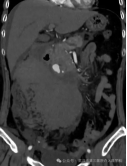

紧急的增强CT检查结果,证实了我们的最坏猜想:肠系膜上动脉的一个分支上,有一个动脉瘤破裂了! 血液正从破口不断涌入腹腔。

您可以把它想象成人体腹腔内一根至关重要“河流”(肠系膜上动脉)的“小支流”管壁上,鼓起了一个小气球(动脉瘤)。这个气球壁比正常的血管壁薄得多,在血流的持续冲击下,它随时可能“爆裂”。

精准导航:在DSA透视的引导下,我们像“巡航导弹”一样,将一根细长而柔软的导管,从股动脉一路精准地“行驶”到肠系膜上动脉,最终抵达破裂的动脉瘤分支。

封堵“决堤口”:通过导管,我们向破裂的动脉瘤及其两端释放了数枚微小的 “弹簧圈” 。这些弹簧圈会迅速在破口处盘绕成团,形成一个致密的“塞子”,瞬间堵死破口,让血液无法再流出。